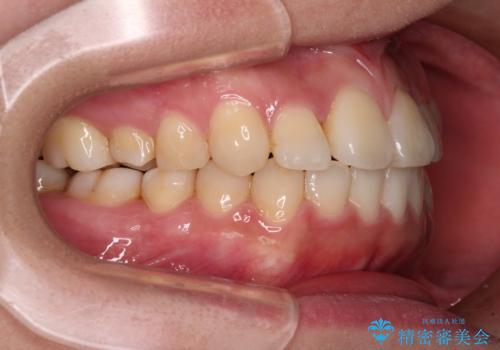

反対咬合とクロスバイトを改善して噛みやすい咬合に

- 前歯のデコボコとクロスバイトを気にして来院された患者様です。

骨格的に下顎が前方位の受け口傾向であり、それが原因でクロスバイトとなっていました。

右奥の歯が180度回転していることで、噛む度にワイヤーに無理な力がかかったようで、頻繁にワイヤーが切れてしまいました。また、下顎を後方に移動させるためのアンカースクリューも脱離することが多く、治療期間が長くなってしまいました。